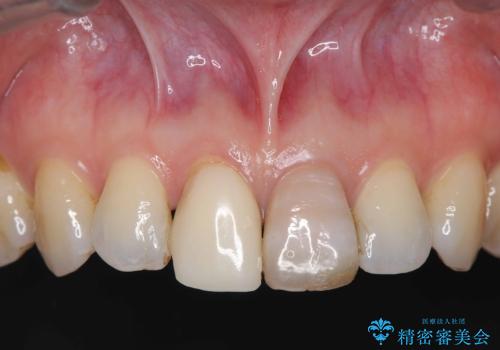

精密根管治療を行い、その後オールセラミッククラウンで審美的に修復しています。あわせてホワイトニングとエアフローによるクリーニングも行い、自然で美しい仕上がりとなりました。

他院で抜歯と診断された歯が、当院での治療により2本とも保存でき、見た目もきれいに仕上がりました。患者様にも大変ご満足いただけました。